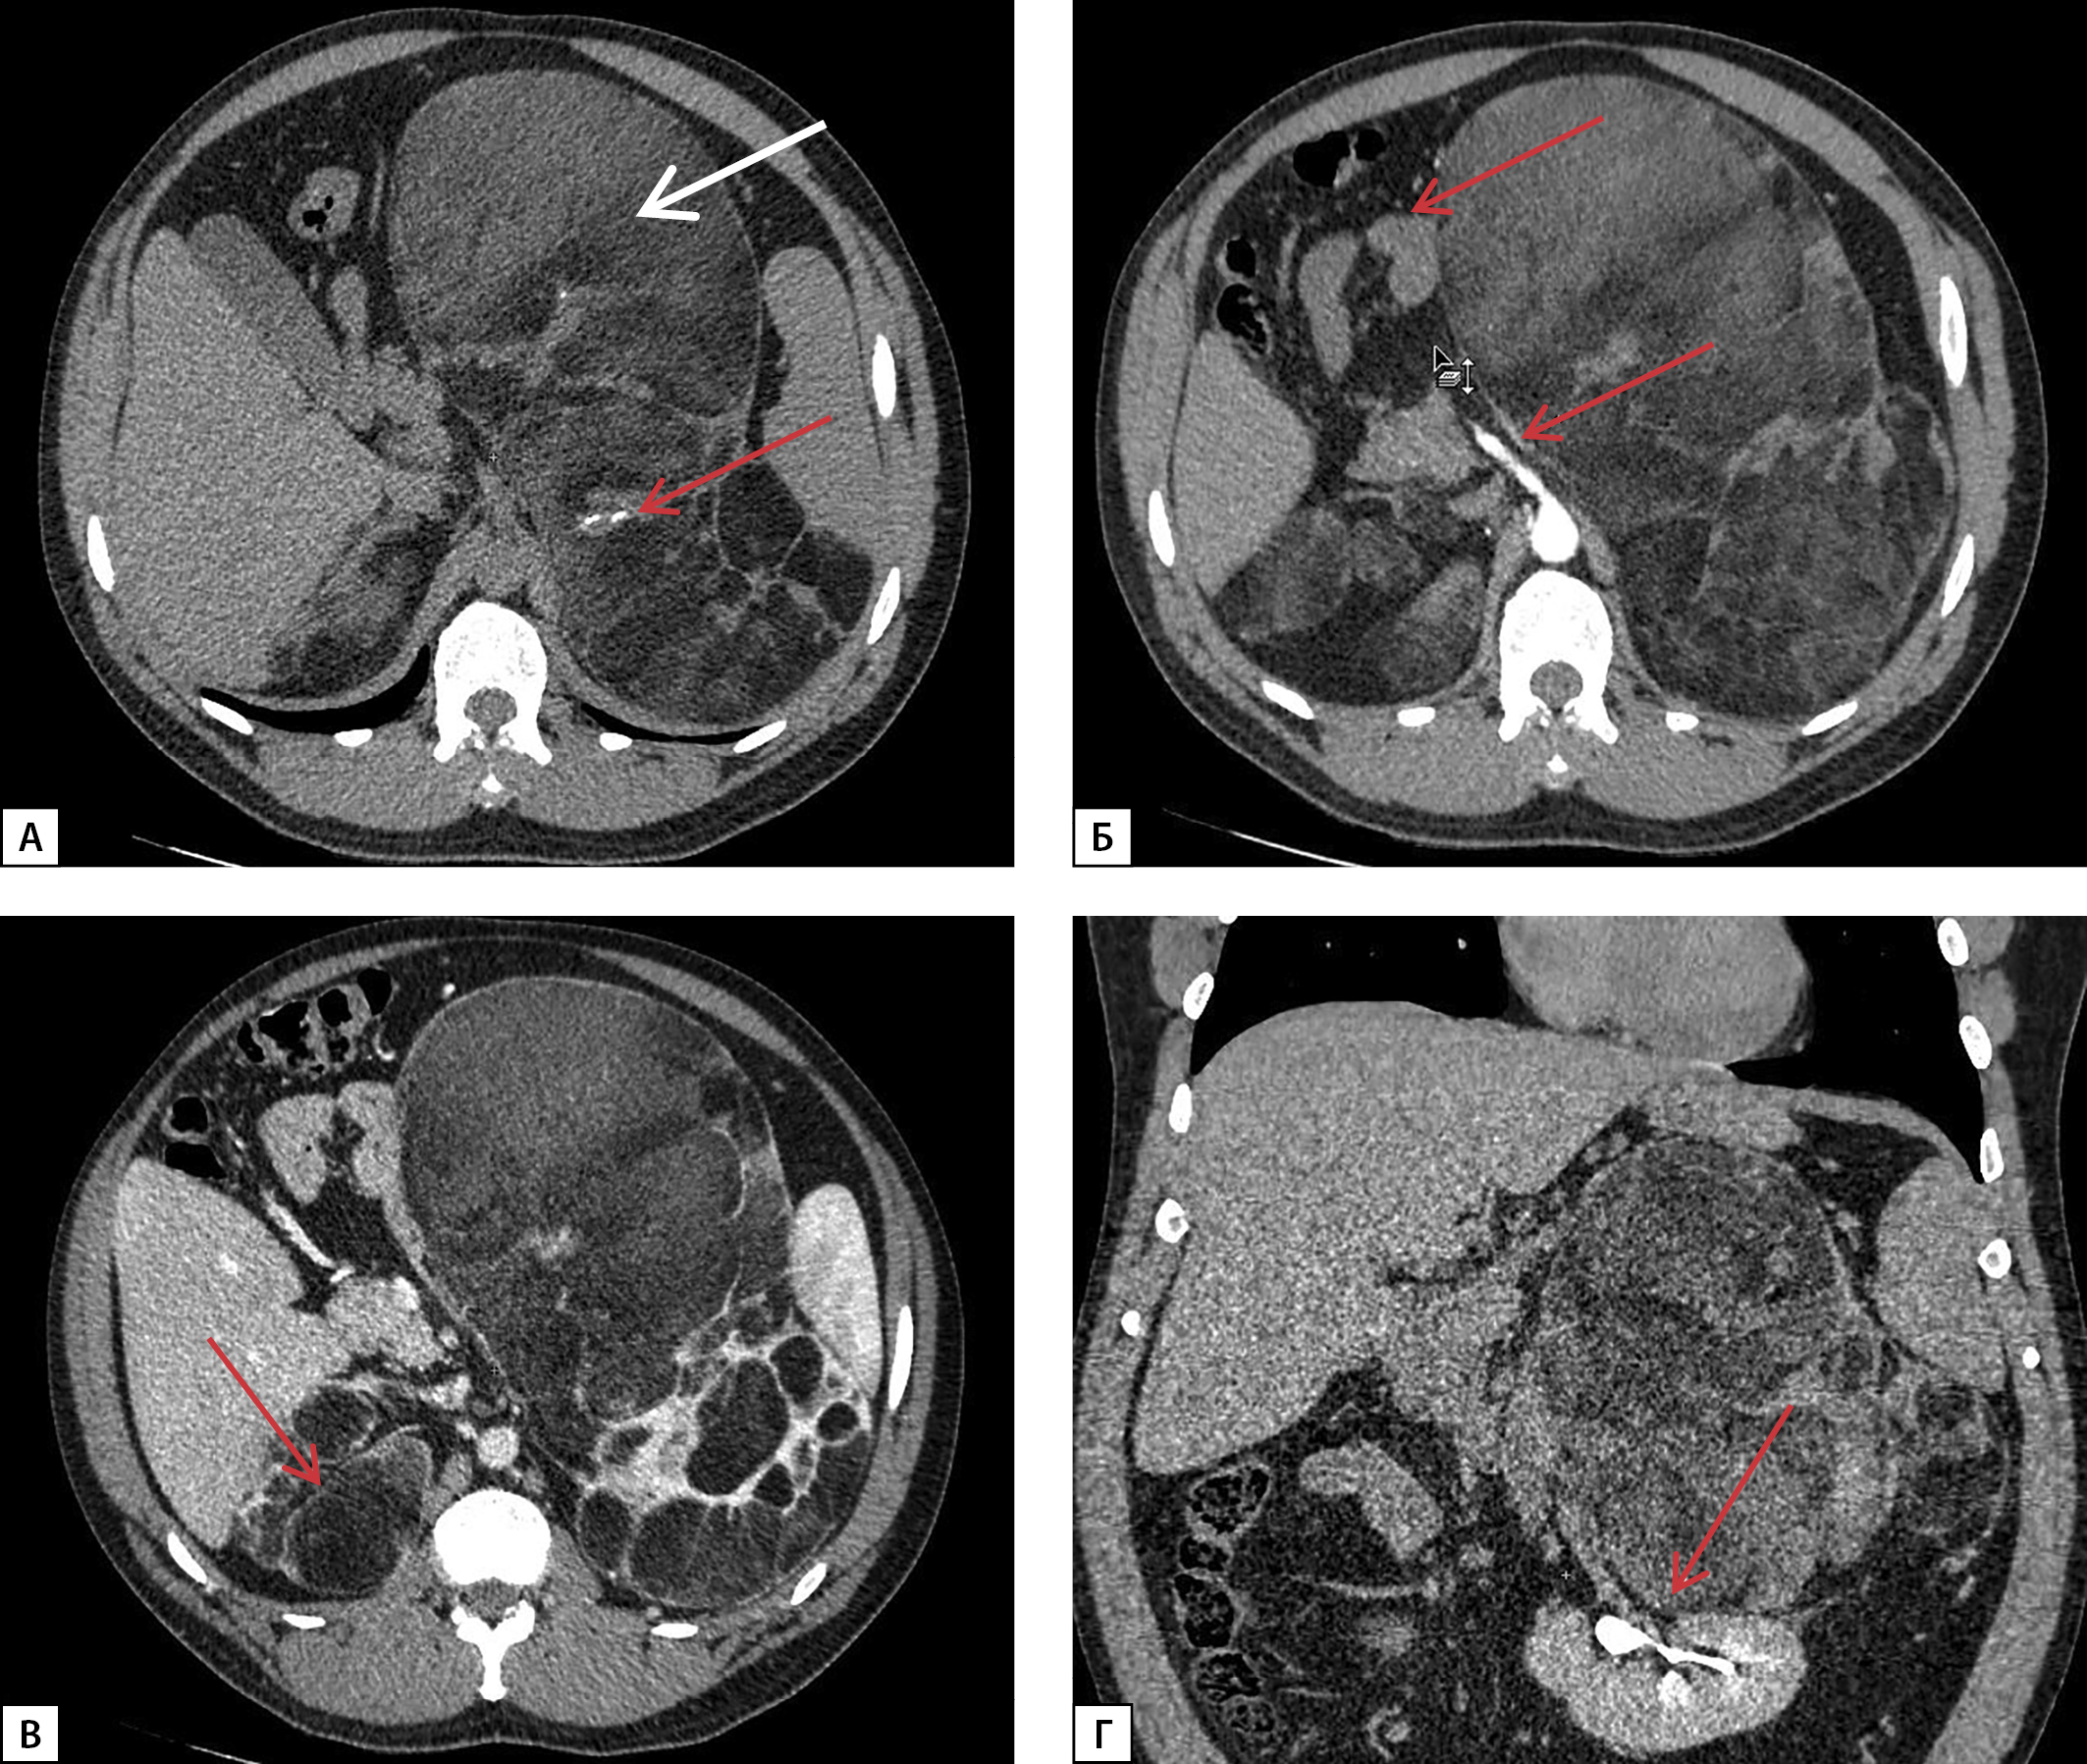

Также в апреле 2019 г. при МСКТ впервые выявлено образование правого надпочечника размерами 11х12х12 см с четкими ровными контурами, без признаков инвазивного роста, неоднородной структуры, плотностью от 5 до 40 ед.Н, накопление только периферическими участками опухоли, в области левого надпочечника — образование размерами 2,2х1,7х1,6 см, с нативной плотностью 13 HU (рис. 6).

Рисунок 6. МСКТ надпочечников, нативная фаза:

А — образование правого надпочечника округлой формы с ровными четкими контурами, наличием кальцинатов в структуре (белая стрелка); Б — образование левого надпочечника с ровными четкими контурами (красная стрелка).

При контрольной явке пациент отмечал нарастание болей в поясничной области. При МСКТ надпочечников без контрастного усиления в октябре 2019 г. в области правого надпочечника выявлено объемное образование неоднородной структуры, плотностью от 16 до 46 HU, размерами 11,9x13,2x12,5 см, в структуре образования визуализировались множественные кальцинаты, преимущественно на периферии, без признаков инвазивного роста, в латеральной ножке левого надпочечника — образование с ровными четкими контурами размерами 2,0x1,7x1,8 см, плотностью от 16 до 23 HU.